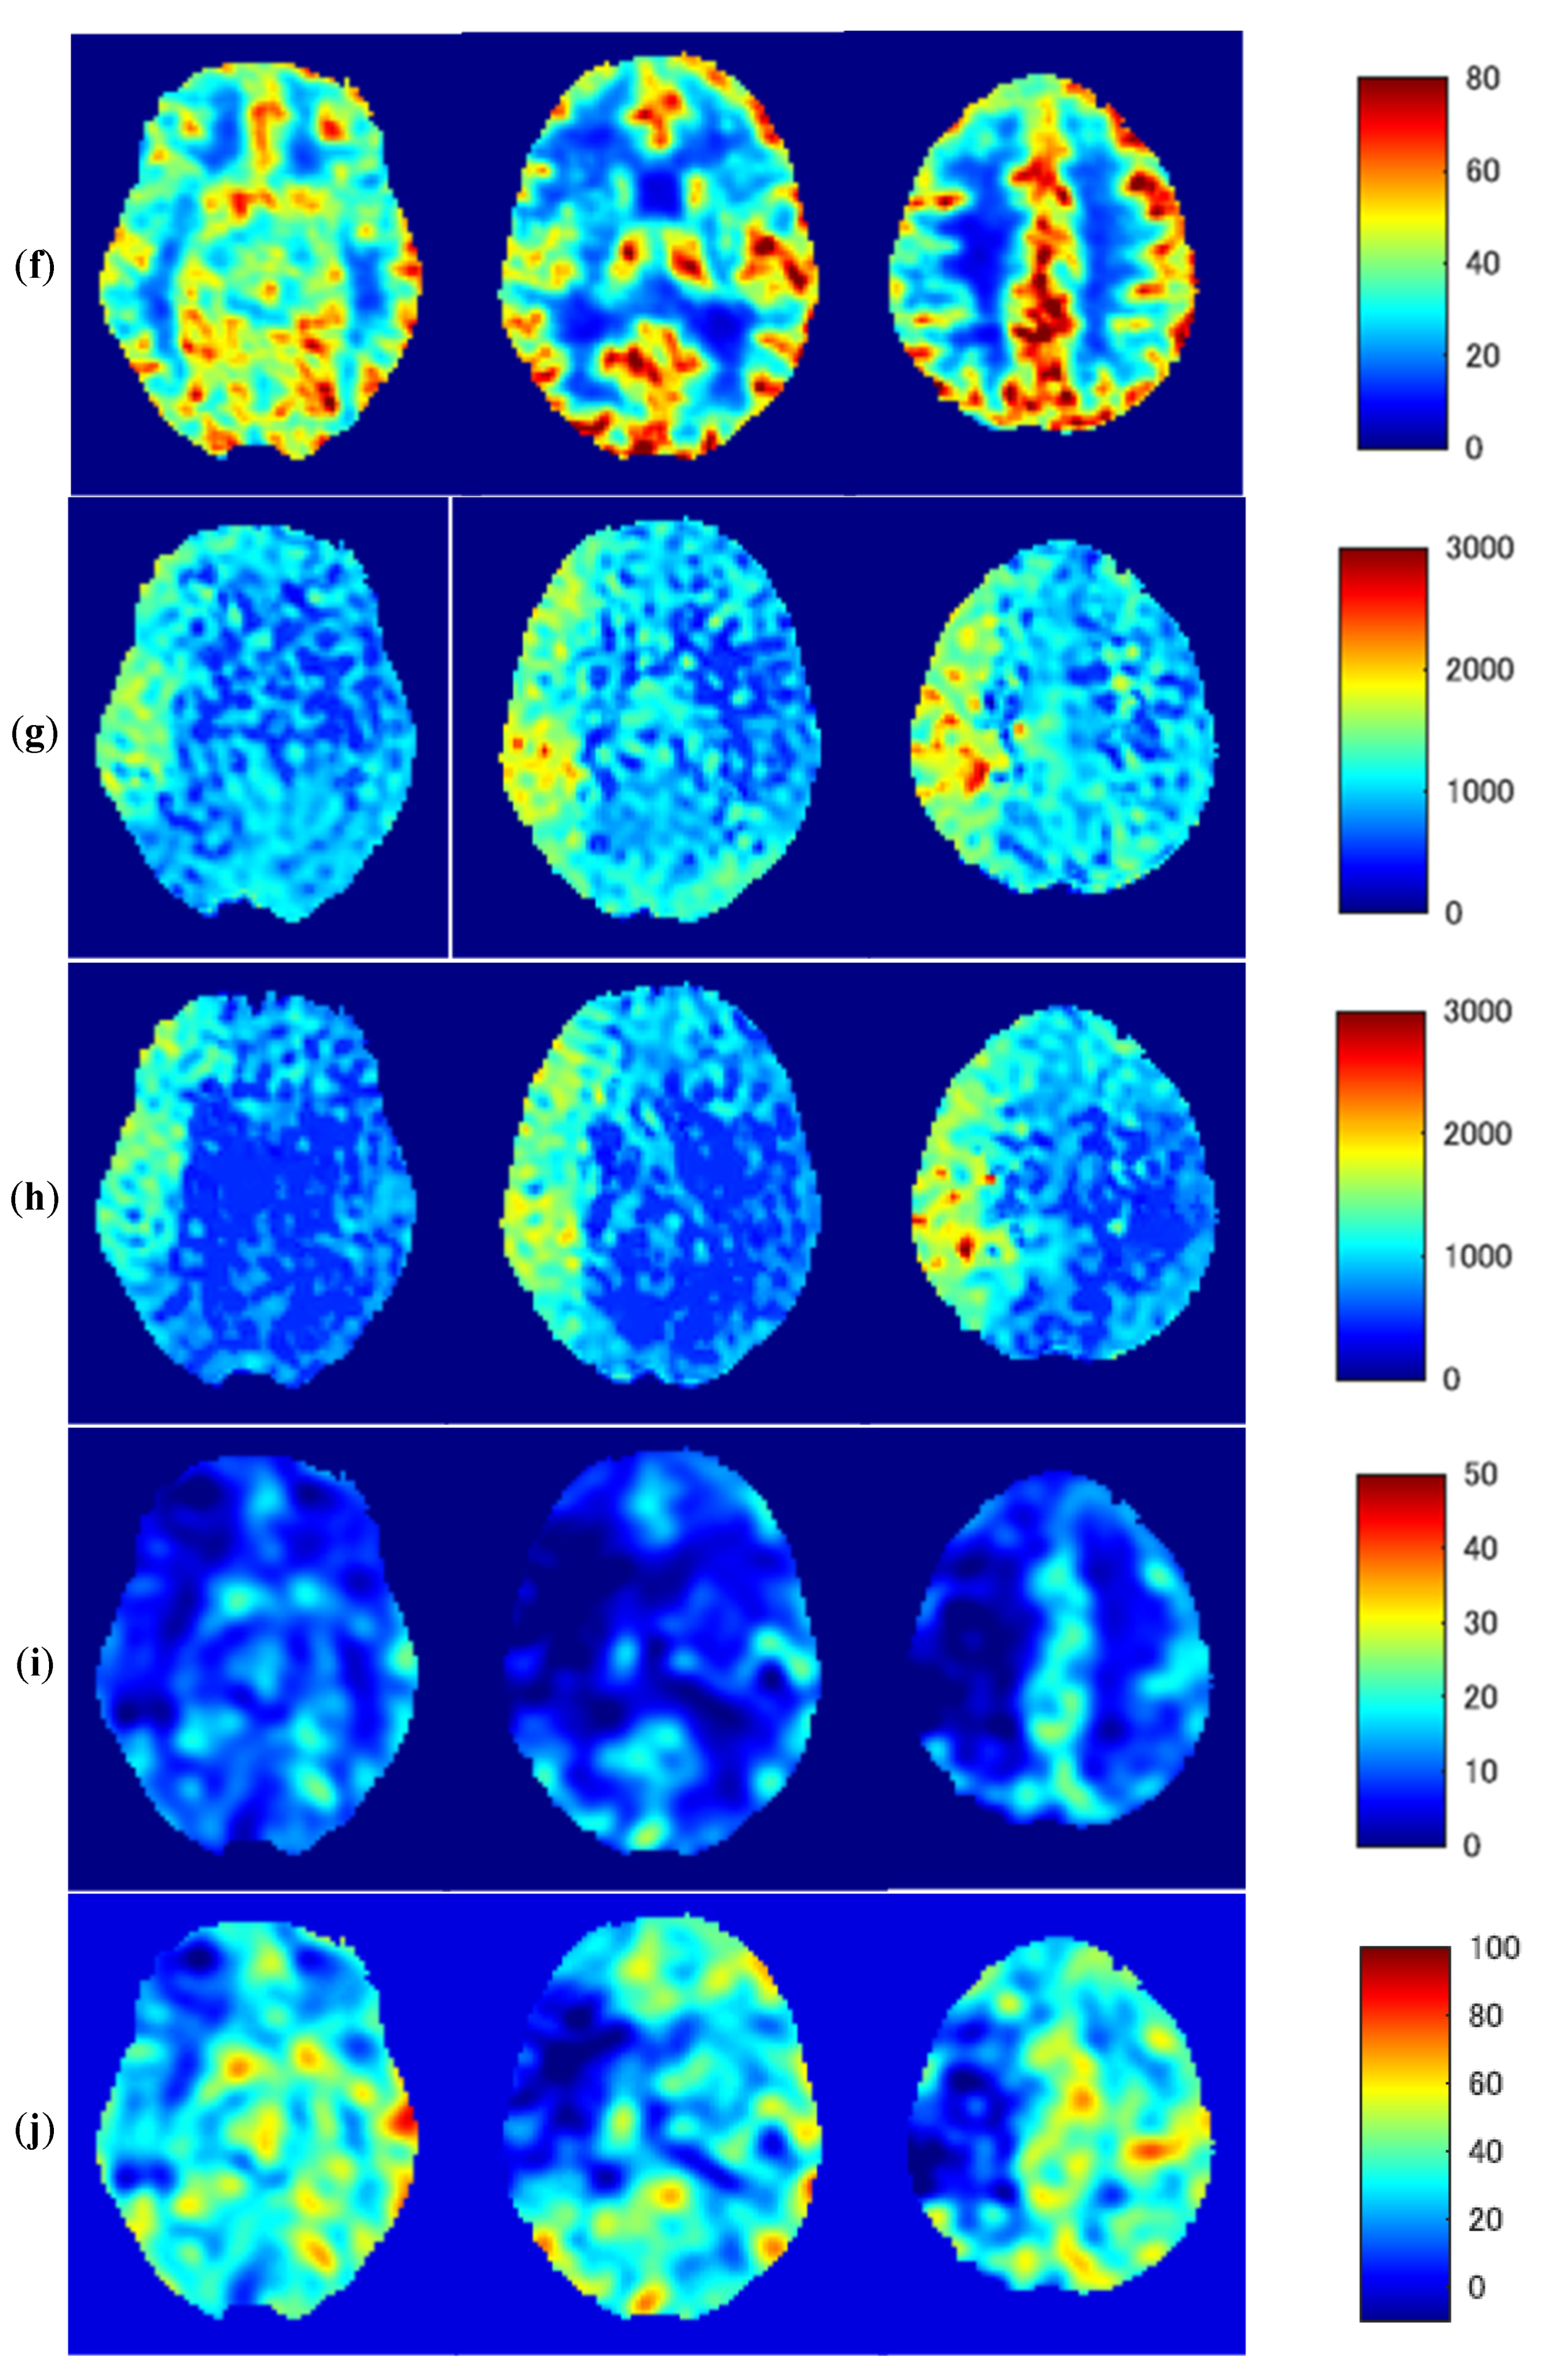

3.3. Representative Images